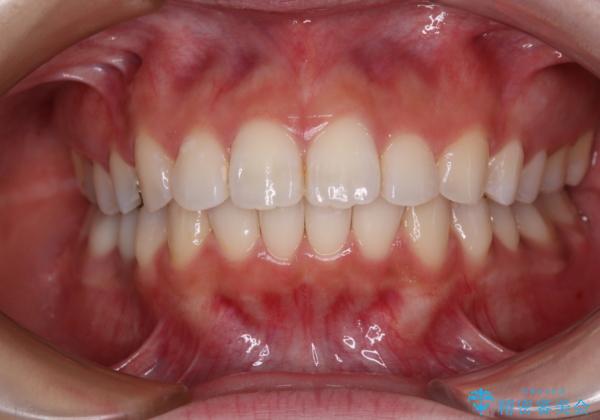

上顎歯列全体を後方移動させたことで唇に当たる感覚は改善され、更には上下の正中位置も合わせることができました。